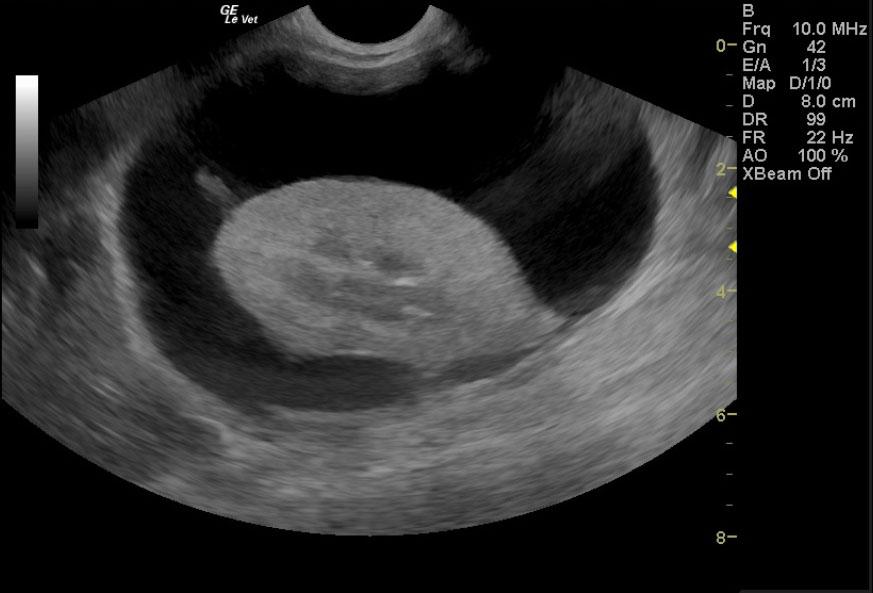

A 17-year-old neutered male DSH cat was presented to the emergency clinic with open-mouth breathing suspected to be secondary to stress/pain as the patient improved on analgesics. On a prior physical examination, an abdominal mass had been palpated.